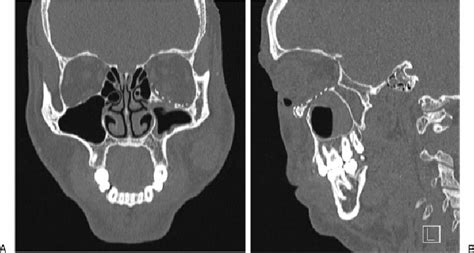

(A, B) Surgical management of the orbital floor fracture ...

(A, B) Surgical management of the orbital floor fracture ... from www.researchgate.net